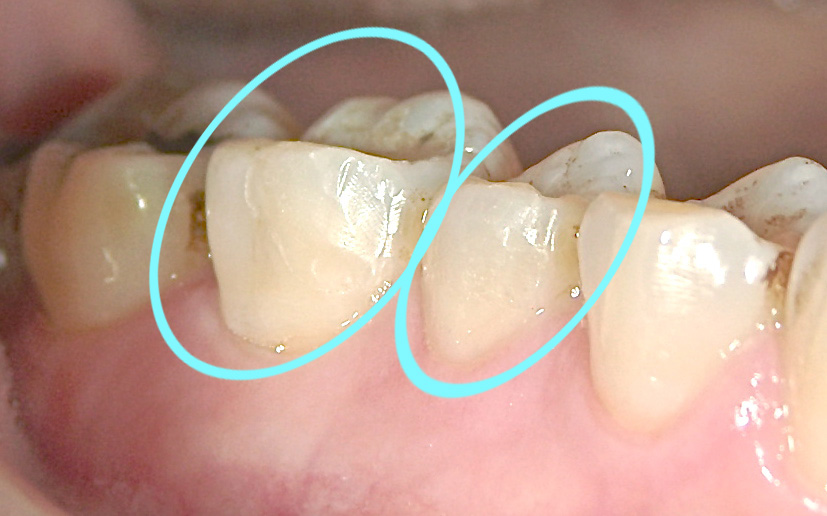

40代の女性。この患者さまの主訴は「こけた時にあごを強打しました。また強く噛み込んだ時の衝撃で、奥歯も欠けてしまいました」でした。

欠けた部分は神経をさわるほど大きくなかったので、まずは応急的に保険のレジン充填(白い詰め物)を欠けた部分に行いました。